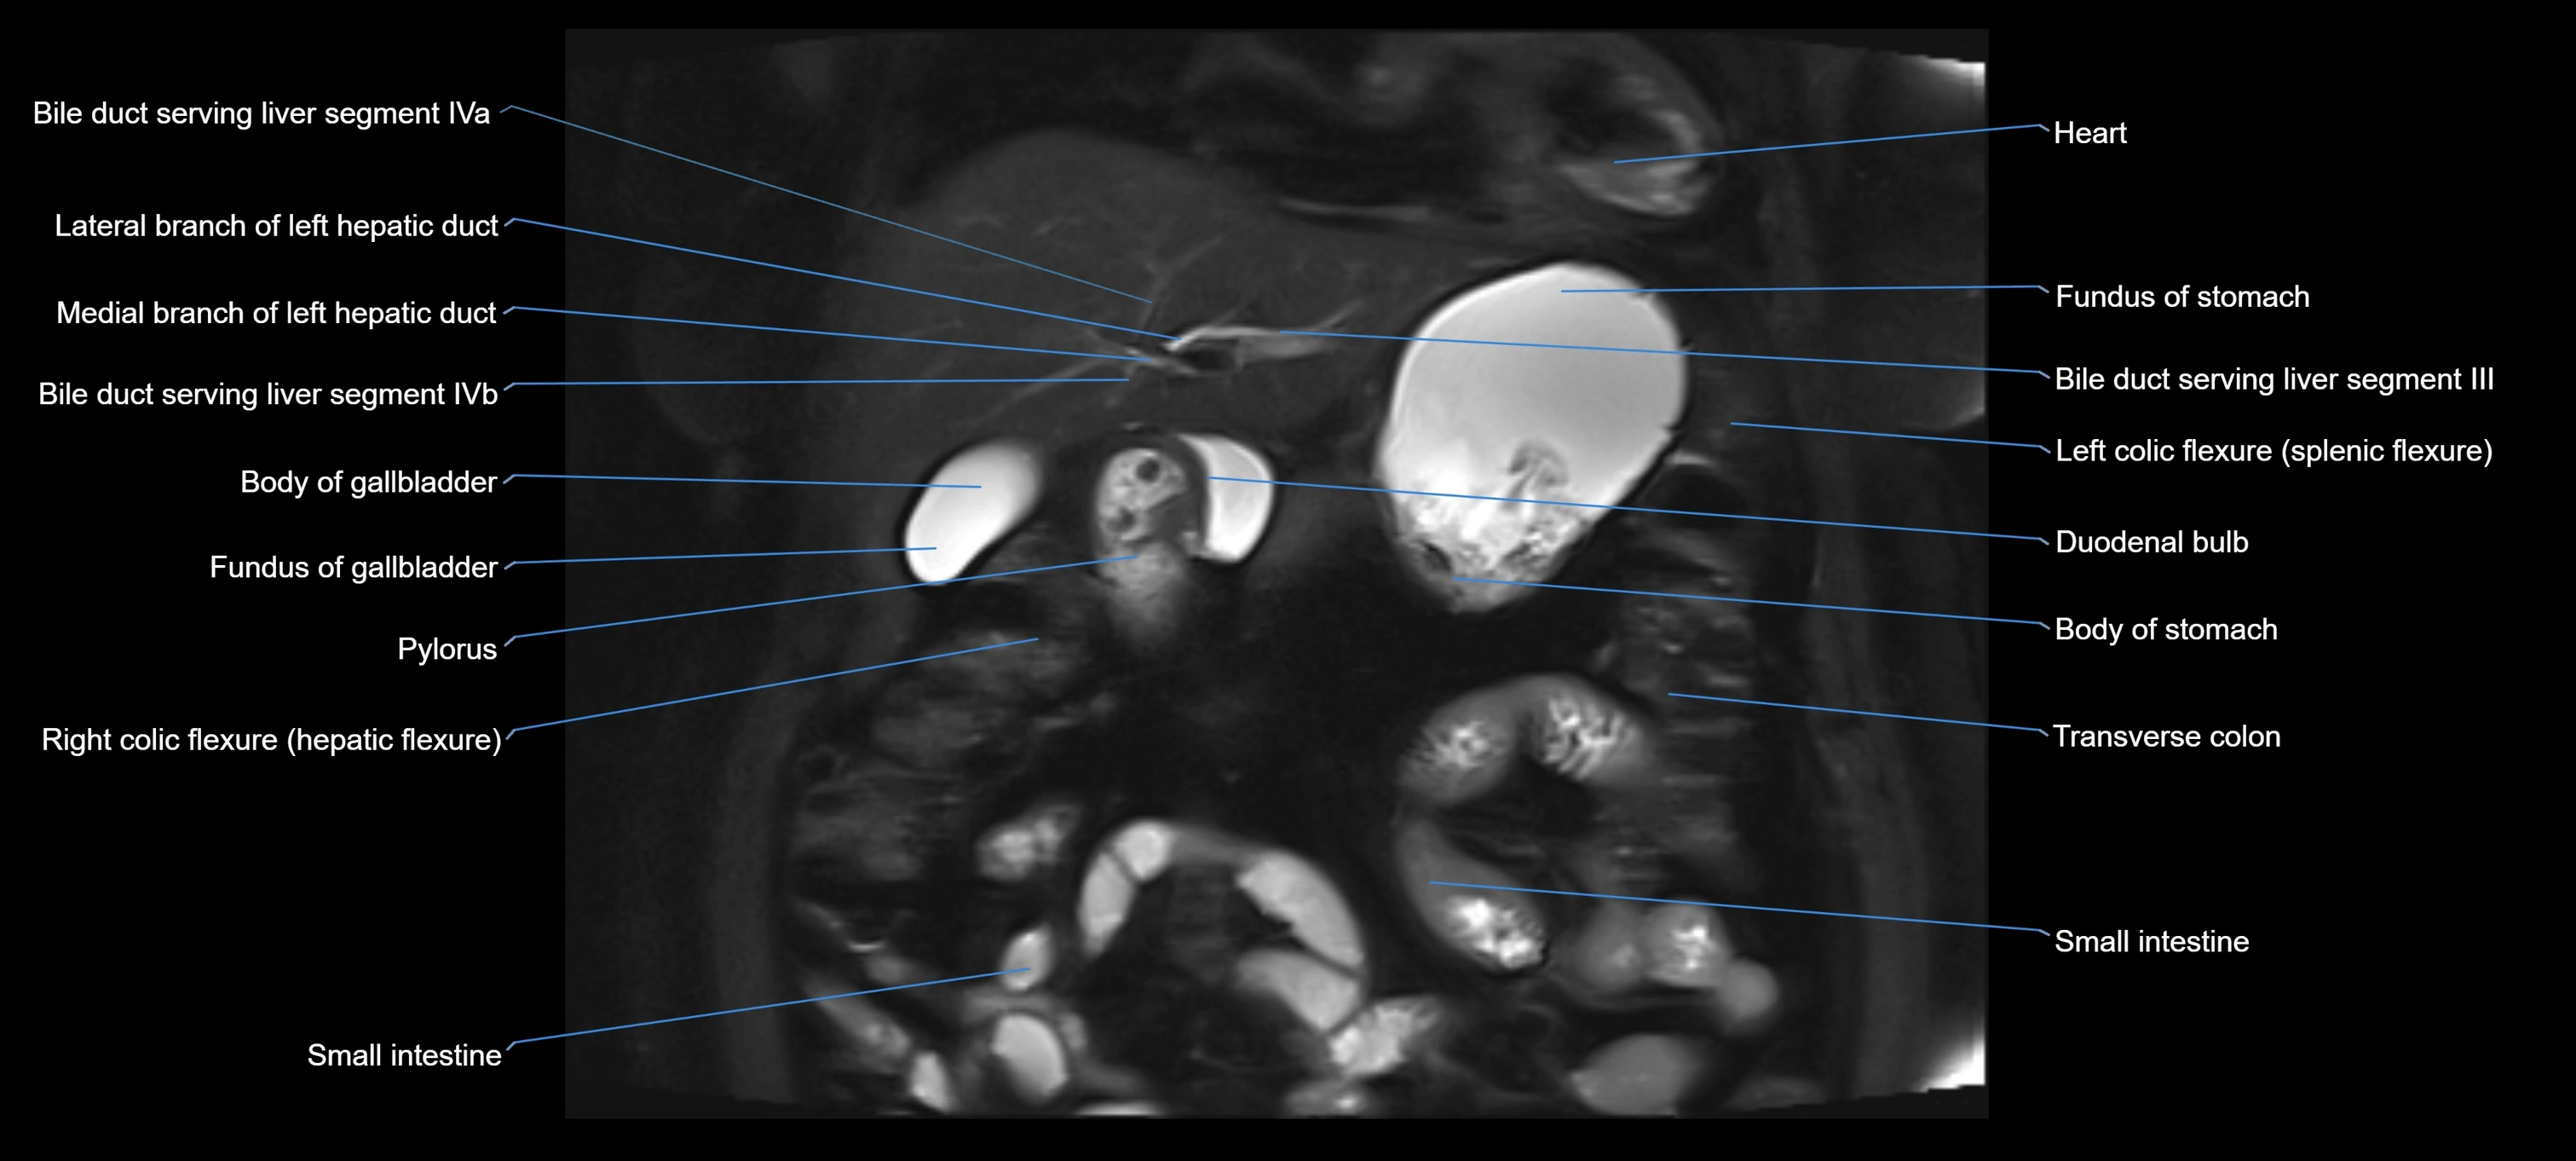

MRI image

image